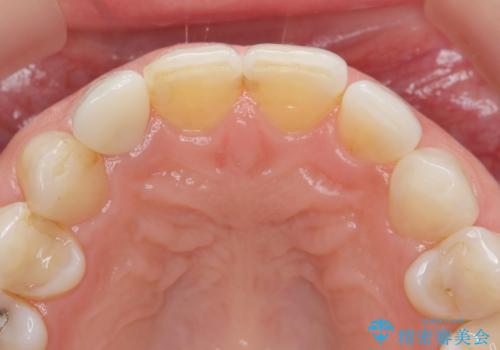

- 前歯の付近、歯ぐきを押すと違和感を感じその改善を求めて来院されました。

X線検査の結果、失活(感染根管)であることが判明したので、感染根管治療後セラミック補綴を計画します。

- 16万円(仮歯・ファイバーコア・ジルコニアクラウンスペシャル)費用は治療当時の料金となります